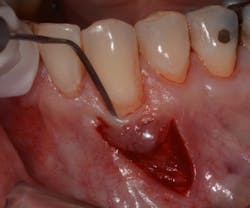

The Bernotti V-Y Flap involves making a submarginal supraperiosteal V-shaped incision 1 mm to 2 mm apical to the mucogingival junction, creating a pedicle flap (figures 2 and 2a). This flap is extended one tooth mesially and distally to the recession defect. It is important to note that the flap should leave the adjacent papillae intact in order to preserve blood supply. An intrasulcular incision is then made with a microsurgical blade to allow for coronal movement of the marginal tissue without tension (figure 3). The root is then scaled/root planed and chemically modified with an amoxicillin slurry for three minutes (figure 3a).

A horizontal mattress suture is then placed in the mucosa, which creates the vertical slope of the Y and advances the marginal part of the flap coronally above the recession defect (figures 4, 4a, and 4b). This tension-free coronal movement of the tissue is obtained by a zipper-like effect of the horizontal mattress (see the video at the end of this article).